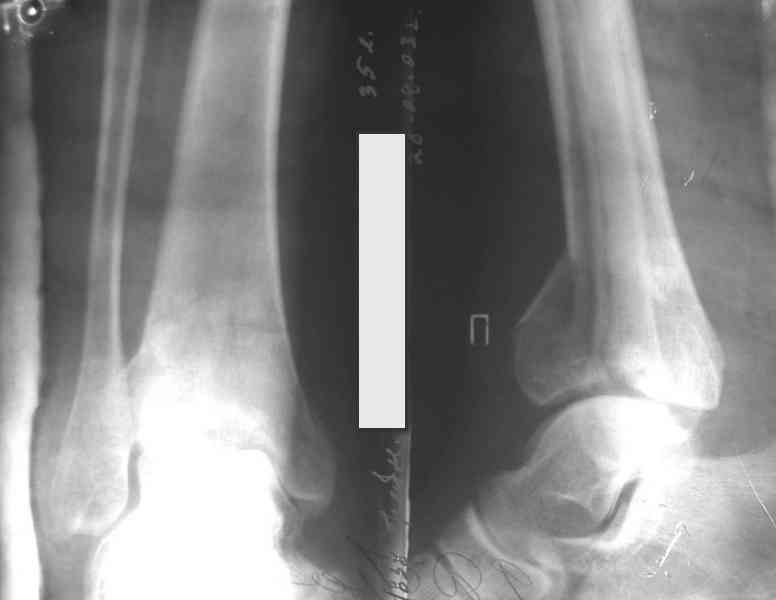

Кстати, при переломах переднего края по классификации АО В-3 при переломах пилона пластина укладывается по передней поверхности. Она достаточно тонкая и эластичная, не надо этого бояться. Посылаю три снимка.